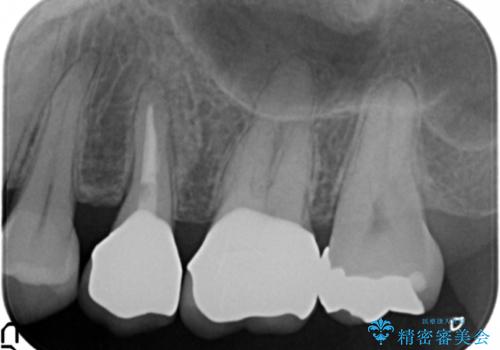

放置し崩壊した歯 セラミック治療による咬合機能回復

虫歯を丁寧に除去したのち、なんとか歯を残せる見通しがたったので根管治療を行いセラミック補綴を行いました。

- 24万円(仮歯×2・ファイバーコア・ジルコニアクラウン×2)費用は治療当時の料金となります

今回は歯を残すことができましたが、早期の治療が歯の長い予後の期待値をあげます。